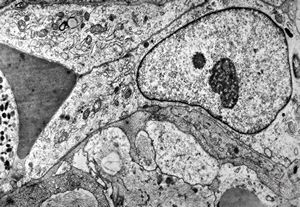

M,10y. | herpetic encephalitis